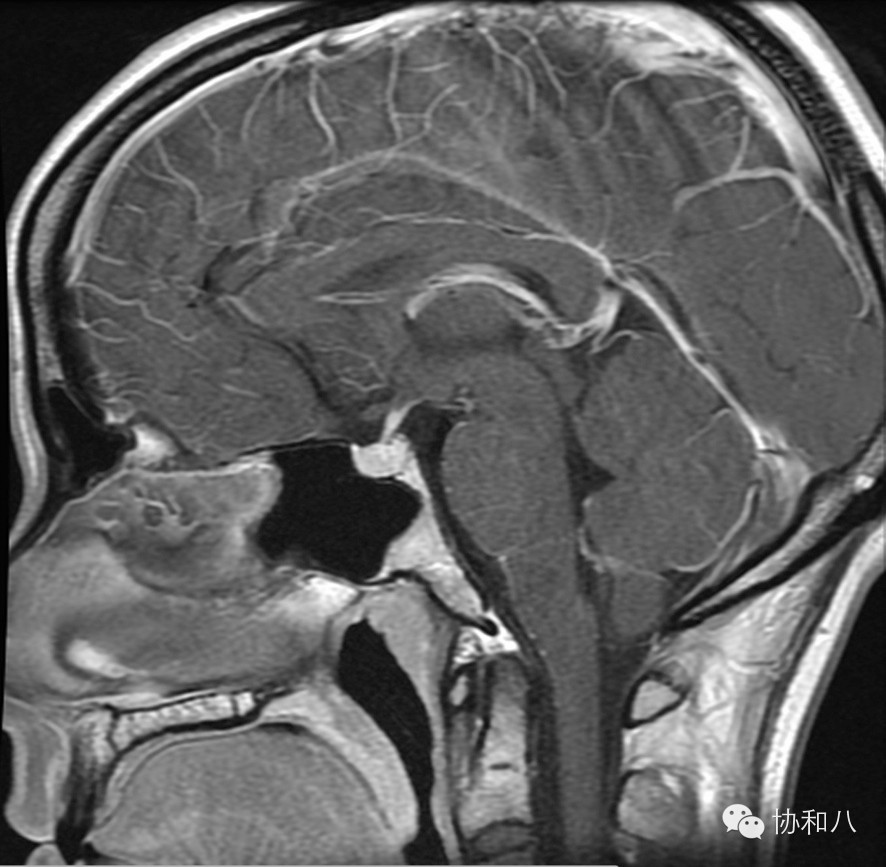

A. 矢状位T1WI

可见垂体增大,在T1W1表现为高信号,符合出血表现